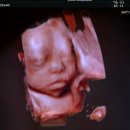

안녕하세요! 이번 포스팅은 임신 29주차 시온여성병원에서 진행한 입체초음파 & 베이비페이스 후기를 남겨보려고 해요 :) 입체초음파는 30주 전에 보는 게...퉁퉁 불어서 정확하게 보기 힘들 수도 있다고 합니다..! 그래서 저도 30주 전인 29주 4일차에 우리 기쁨이 얼굴을 보고 왔어요😄 그럼 29주차 입체...

luv_Joy(2026-02-15 02:01:00)